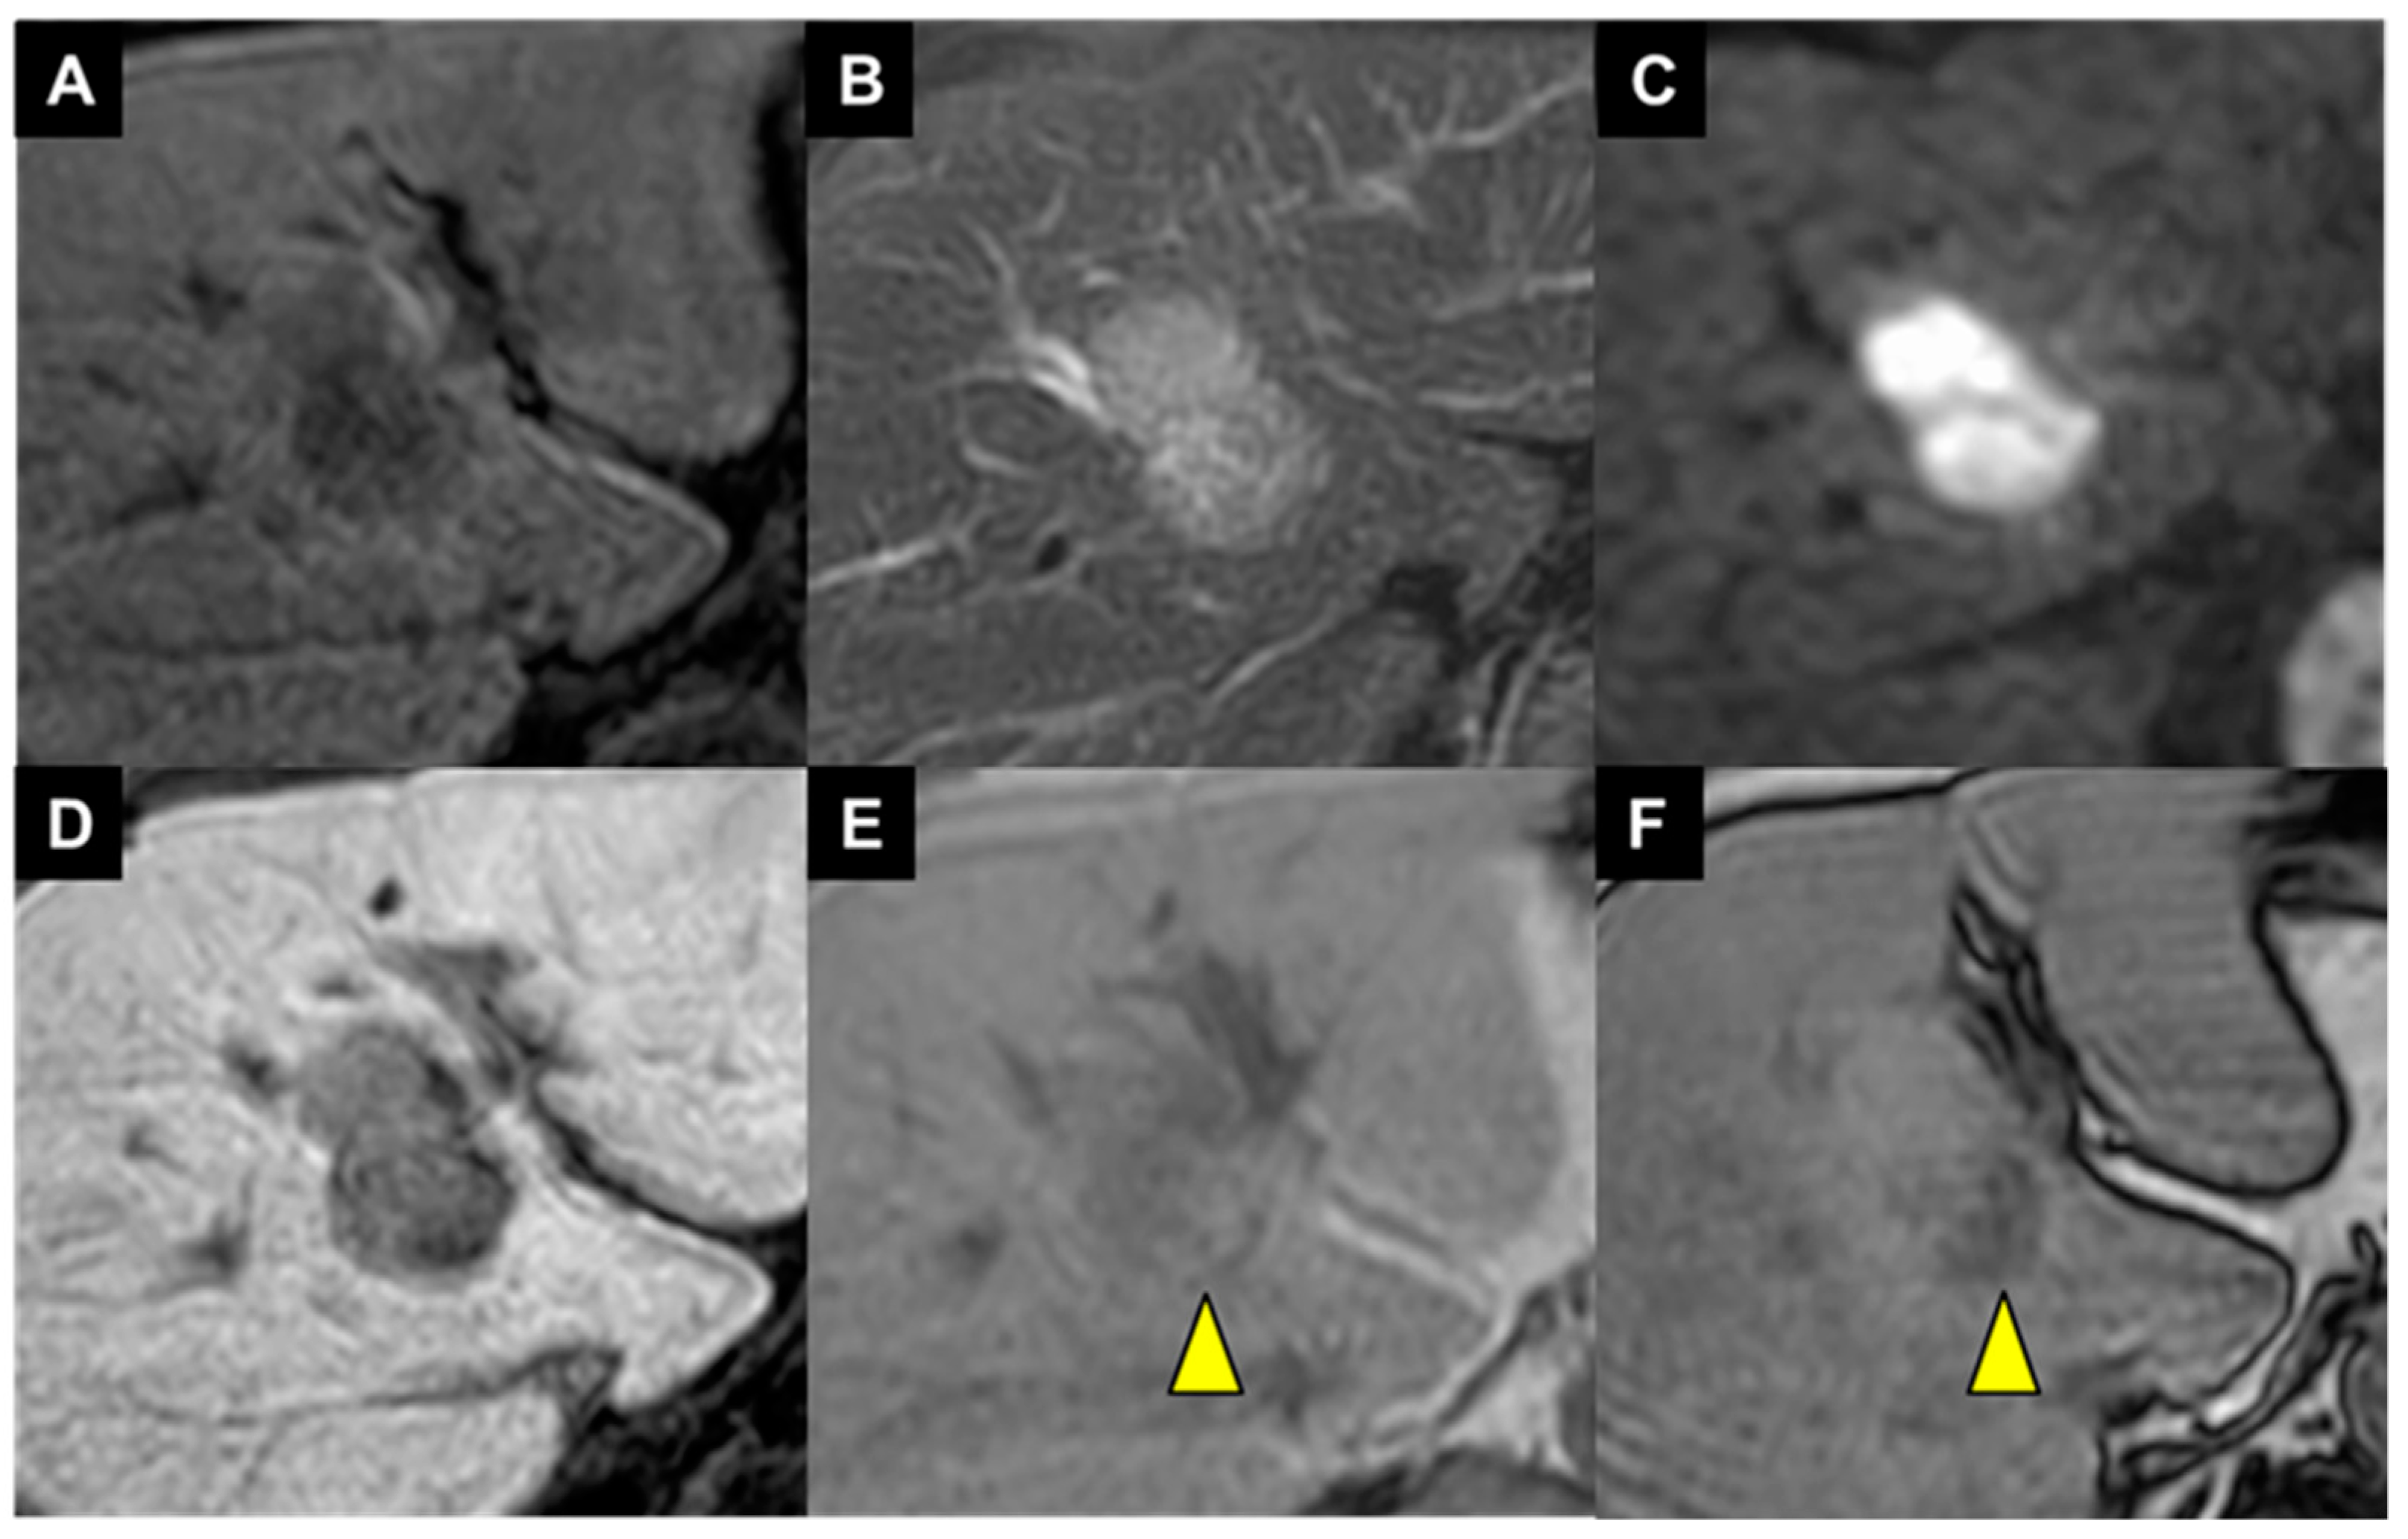

- Muraishi, N.; Kawamura, Y.; Akuta, N.; Shindoh, J.; Matsumura, M.; Okubo, S.; Fujiyama, S.; Hosaka, T.; Saitoh, S.; Sezaki, H.; et al. The Impact of Lenvatinib on Tumor Blood Vessel Shrinkage of Hepatocellular Carcinoma during Treatment: An Imaging-Based Analysis. Oncology 2023, 101, 134–144. [Google Scholar] [CrossRef]